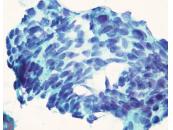

第40回日本臨床細胞学会九州連合会学会(大分)スライドカンファレンス症例3

種別:泌尿器

出題:橋向 圭介 熊本大学病院病理部

| 年齢 | 70代 | 性別 | 男性 |

| 採取部位 | 分腎尿 | 採取方法 | カテーテル |

| 検体処理法 | 2回遠心法(YM式液状検体固定液) |

既往歴:胸椎多発性骨髄腫治療中

現病歴:2021年より胸椎多発性骨髄腫の化学療法中であり、治験前スクリーニングの単純CT検査にて左尿管軟部影を指摘。同時期に腰痛、水腎症が出現し、精査目的のため分腎尿が提出された。

| 正解 | 5.形質細胞腫 |

▼選択肢及び投票結果

| 1.ウイルス感染細胞 | 21件 | (20.0%) | |

| 2.低異型度尿路上皮癌 | 8件 | (7.6%) | |

| 3.高異型度尿路上皮癌 | 30件 | (28.6%) | |

| 4.小細胞癌 | 3件 | (2.9%) | |

| 5.形質細胞腫 | 43件 | (41.0%) | |

| 投票総数 | 105件 | (100%) |